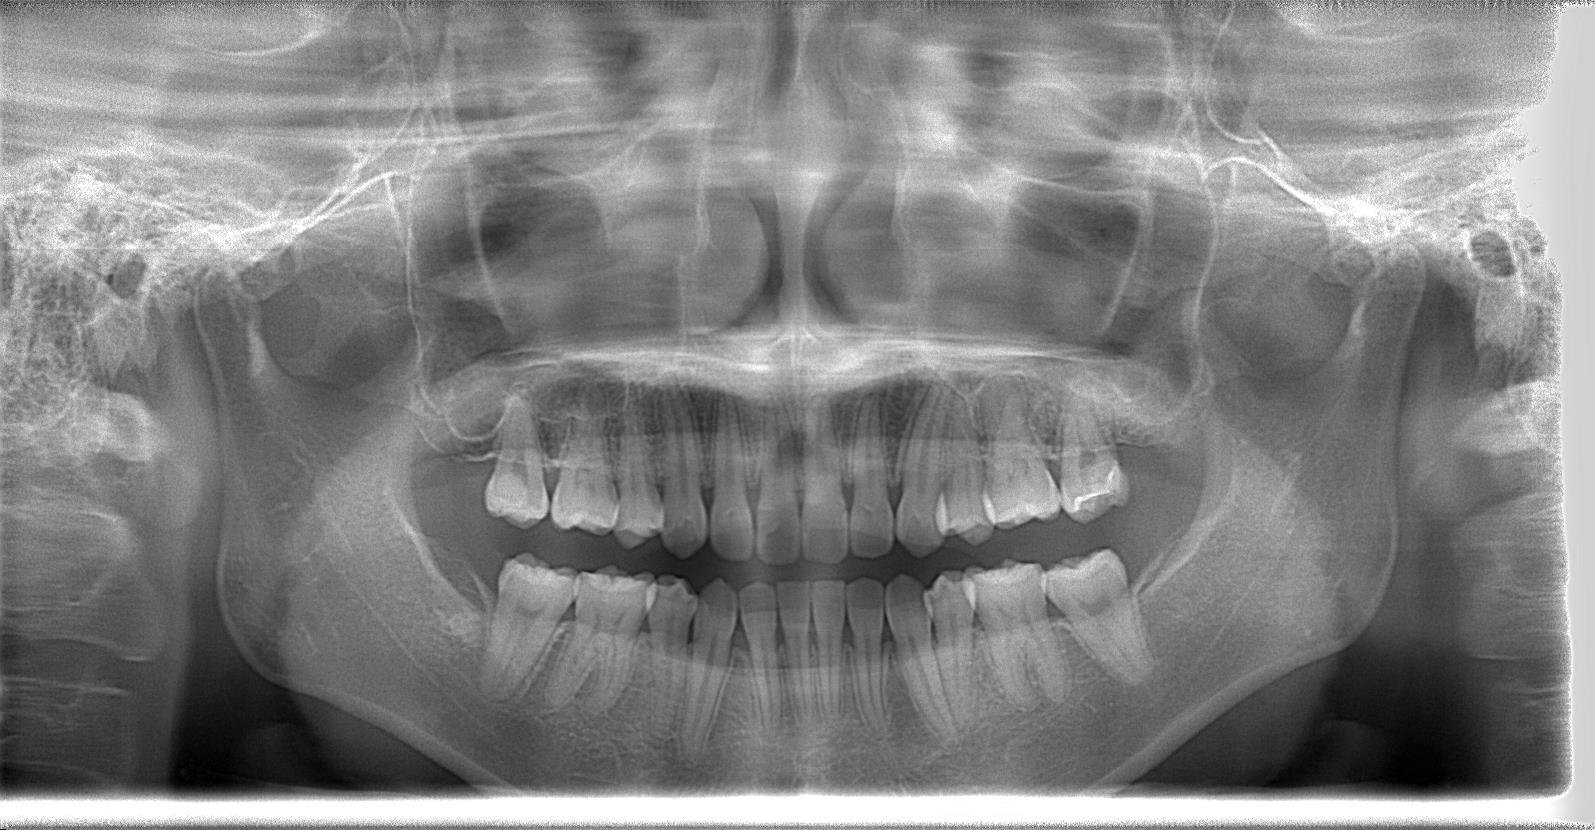

術後パノラマレントゲン写真

抜歯後は、経過良好です。